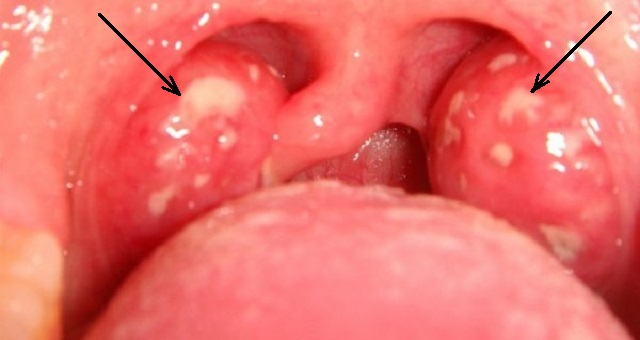

Στρεπτόκοκκος

Αυτό το βακτήριο ταξιδεύει μέσω του αέρα και μπορεί να μεταφερθεί μέσω του φιλιού ή ακόμα και όταν κάποιος φτερνίζεται.

Αυτό το βακτήριο ταξιδεύει μέσω του αέρα και μπορεί να μεταφερθεί μέσω του φιλιού ή ακόμα και όταν κάποιος φτερνίζεται.